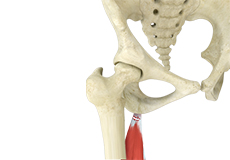

Hamstring Injuries

Hamstring injuries occur when these muscles are strained or pulled. They are common in dancers and athletes of all sorts including runners and those who play football, soccer, basketball, tennis, etc.